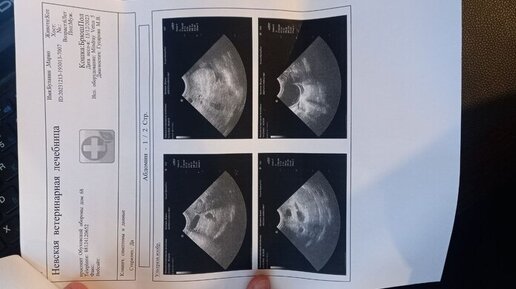

Добрый времени суток Нужна консультация ветонколога Коту (6 лет) диагностировали рак печени. Печень сильно увеличена, как сказал врач на снимках чёрные пятна это метостазы, но кот себя чувствует хорошо, ест и пьёт как обычно, с туалетом проблем нет, в поведении и состоянии отклонений нет, единственное что было это когда он долго лежит, потом встаёт и его штормит, как будто пьяный, такое было замечено пару раз...